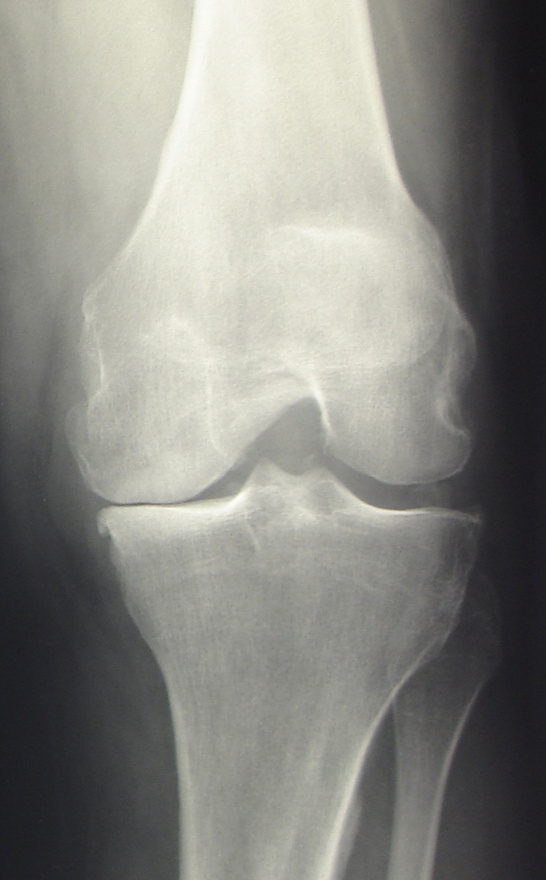

Diese Operationen werden dann durchgeführt, wenn andere konservative Maßnahmen (Medikamente, Physiotherapie, Spritzen) keine ausreichende Schmerzlinderung mehr bringen, auf dem Röntgenbild eine Arthrose nachweisbar ist und sich die Gelenkfunktion verschlechtert hat. Häufigste Ursache für den Verschleiß eines Gelenkes ist die Arthrose. Hierbei unterscheidet man primäre und sekundäre Formen. Die Entstehung der häufigsten – primären – Arthrose ist noch immer nicht vollständig geklärt. Sekundär kann der Gelenkverschleiß nach anderen Krankheiten, z.B. Gelenkinfektionen, bei chronisch entzündlichen Gelenkerkrankungen, bei Formfehlern, Achsabweichungen oder nach Verletzungen auftreten.

Der künstliche Kniegelenkseratz (KTEP) ist die zweithäufigste endoprothetische Operation. Dieses Verfahren führen wir stationär im Carl-Thiem-Klinikum Cottbus durch. Dieses OP-Verfahren können wir Ihnen im Rahmen unseres innovativen ORTHOPAEDICON FAST TRACK Konzeptes (LINK!) im Krankenhaus Spremberg ambulant anbieten. Alle Patienten, für die eine ambulante Versorgung nicht geeignet ist, versorgen wir an der Medizinischen Universität Lausitz Carl Thiem in Cottbus: nach ERAS Kriterien, mit modernsten Implantaten und einer strukturierten Vor- und Nachbetreuung.

Bei der Kniegelenksarthrose wird die verschlissene Knorpeloberfläche der Gelenkpartner durch eine Metalloberfläche ersetzt („Oberflächenersatz“). Als Gleitschicht zwischen beiden Komponenten dient ein sog. Inlay aus Polyethylen.